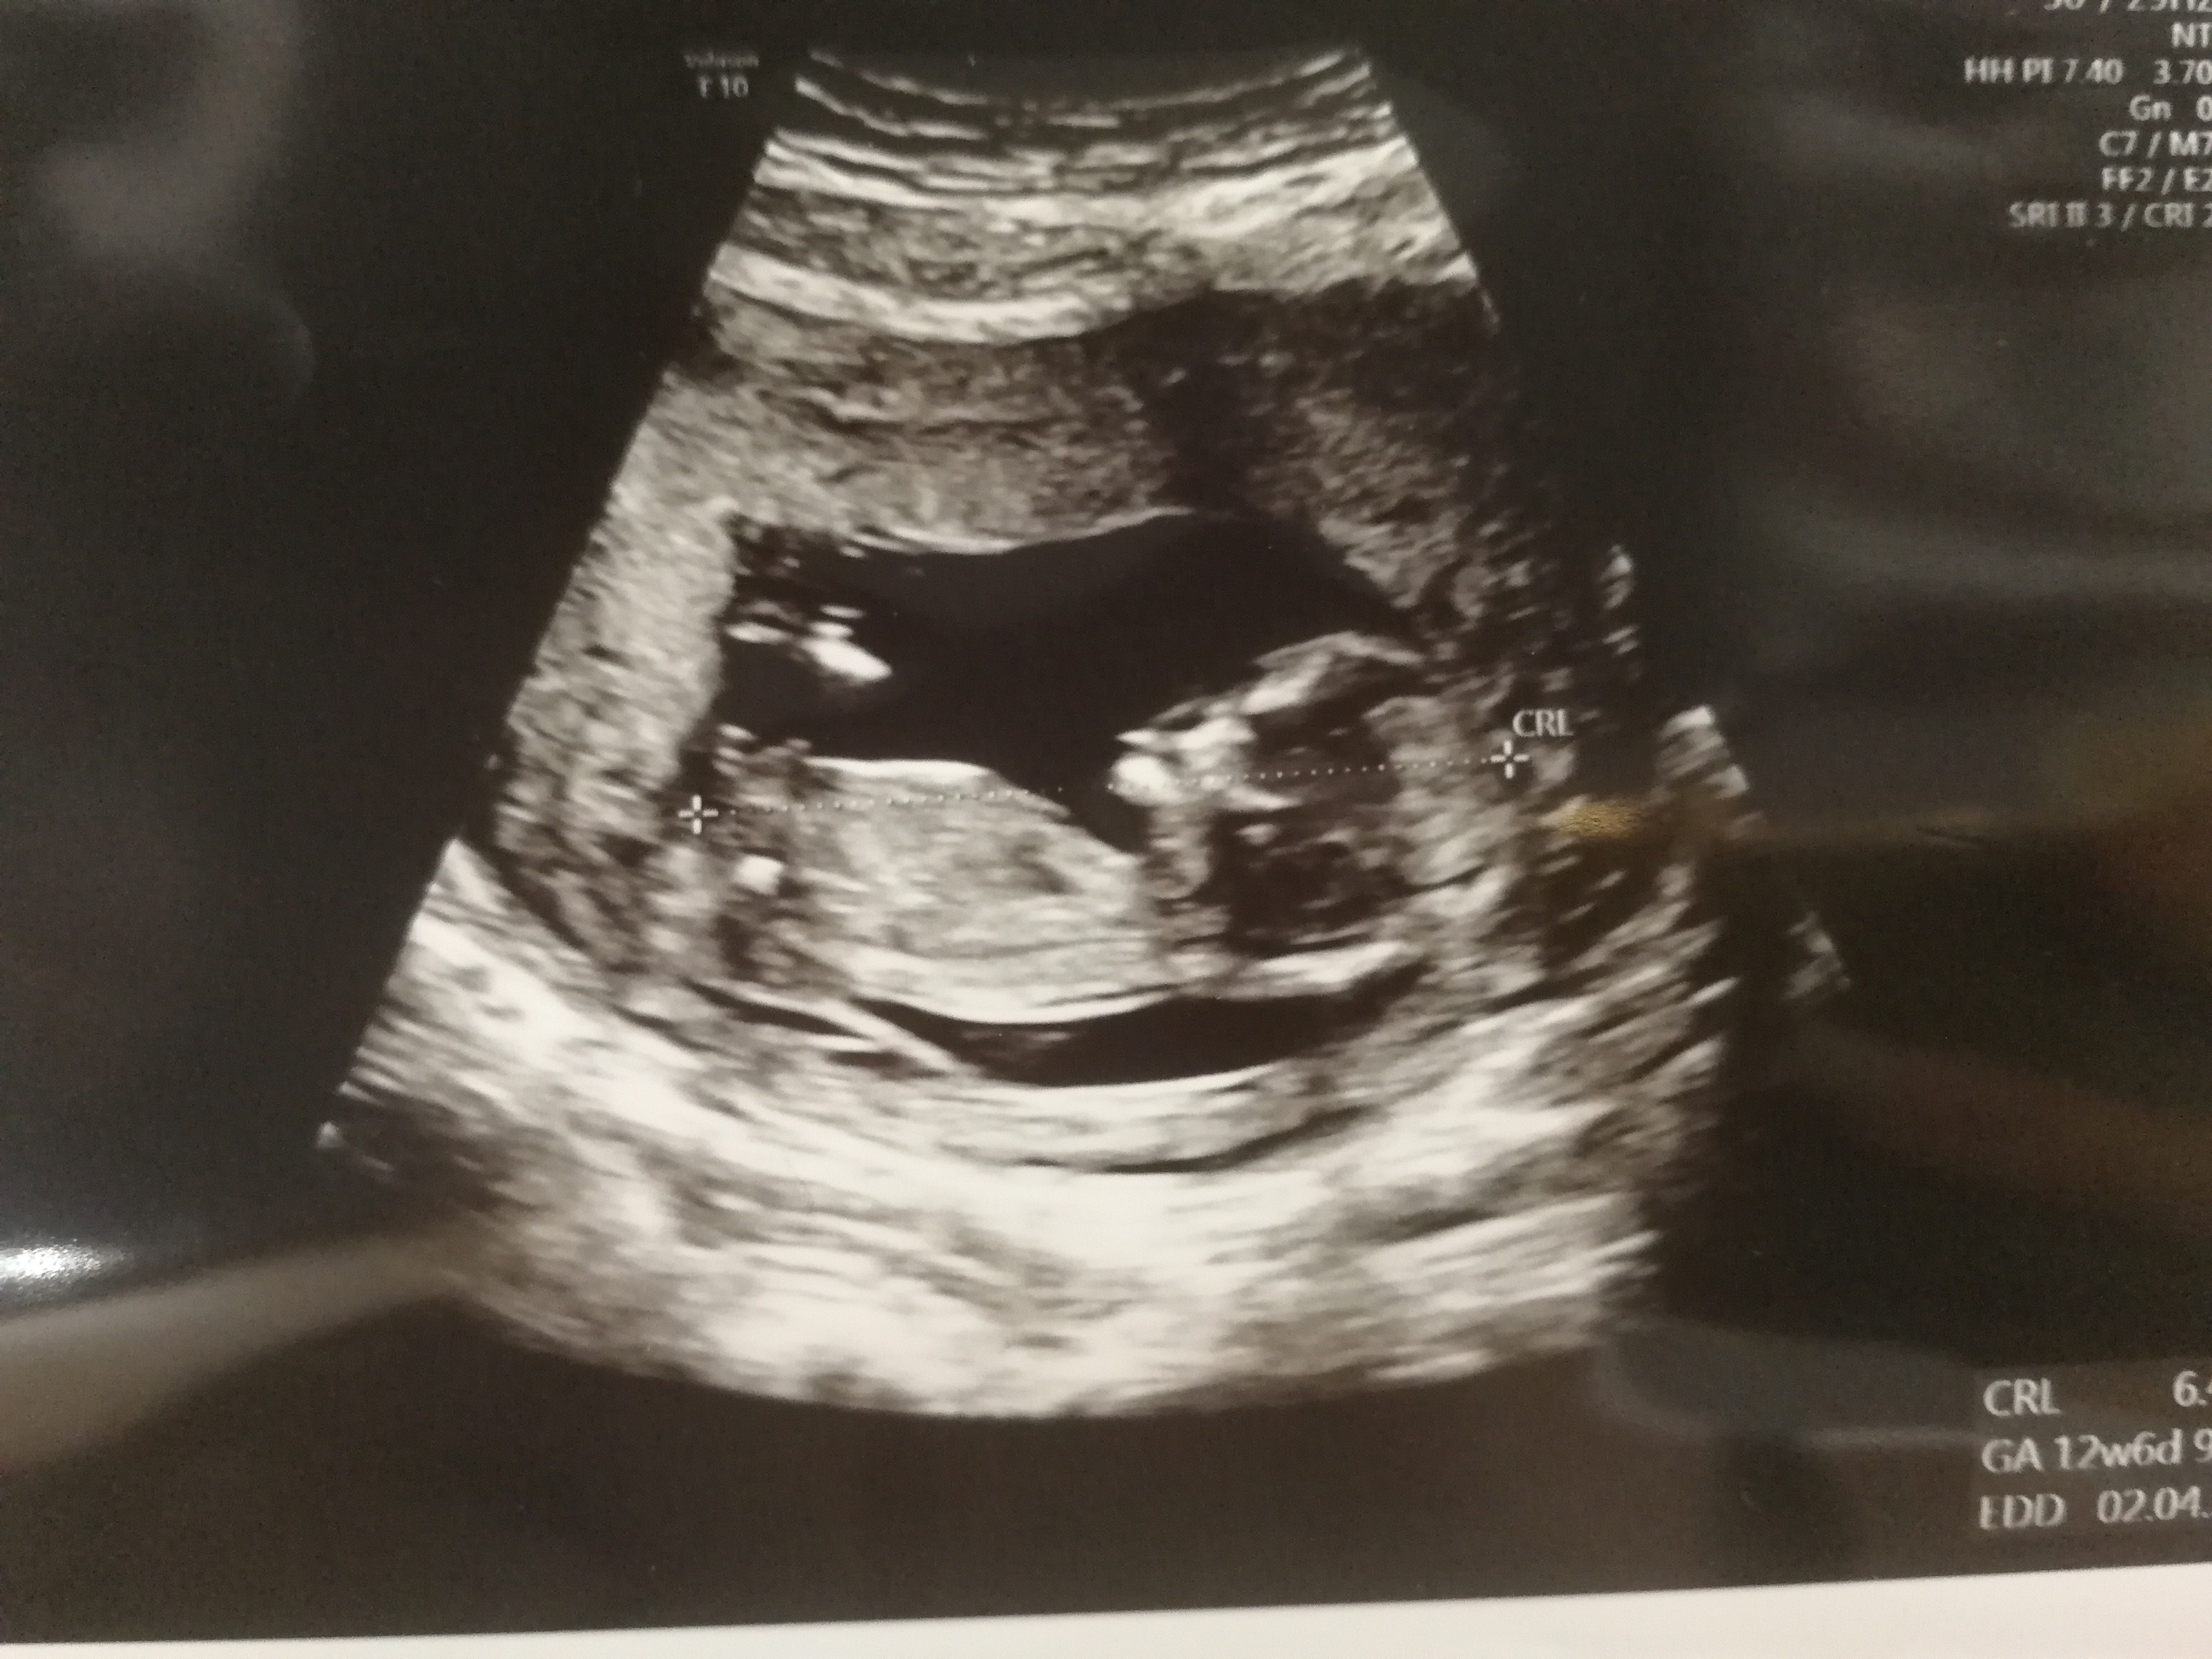

Zacznijmy od tego, że z mężem mamy taką grupkę znajomych. Razem z nami 4 pary. Wraz z jedną z tych par zaszliśmy w ciążę w listopadzie zeszłego roku. Ona donosiłam, ja niestety nie. Wiem ile nerwów kosztowała mnie jej ciąża i mimo wszystko byłam cholernie zazdrosna. Powiedziałam mężowi, że jak nie zajdę w ciążę przed jej porodem to niech szykuje bilet do psychiatryka bo ja nie dam sobie z tym rady. Człowiek niby rozumie, wie, że to głupie, ale uczucia są silniejsze. W międzyczasie dowiedzieliśmy się, że kolejna para również straciła ciążę w czerwcu. Co najgorsze niedawno napisała do mnie ta znajoma - pytała się czy bać się łyżeczkowania. Niestety znowu stracili swoje maleństwo. Także byłaby kwiwtniowką. O naszej ciąży jeszcze tylko oni nie wiedzą. W sobotę idziemy wszyscy na 30 kolegi. I to jest moje pytanie... Jak i czy wogole powiedzieć im o ciąży? Głupio mi ich okłamywac gdy zapytają jak tam w pracy i co u nas. Szczególnie że że jakiś czas spotkamy się znowu i już ciąży nie ukryje. Reszta znajomych dostała nakaz milczenia. Sama nie wiem co robić.. I nie wiem czy chciałbym dostać taka wiadomość 3 tygodnie po zabiegu.. Pomocy ☹